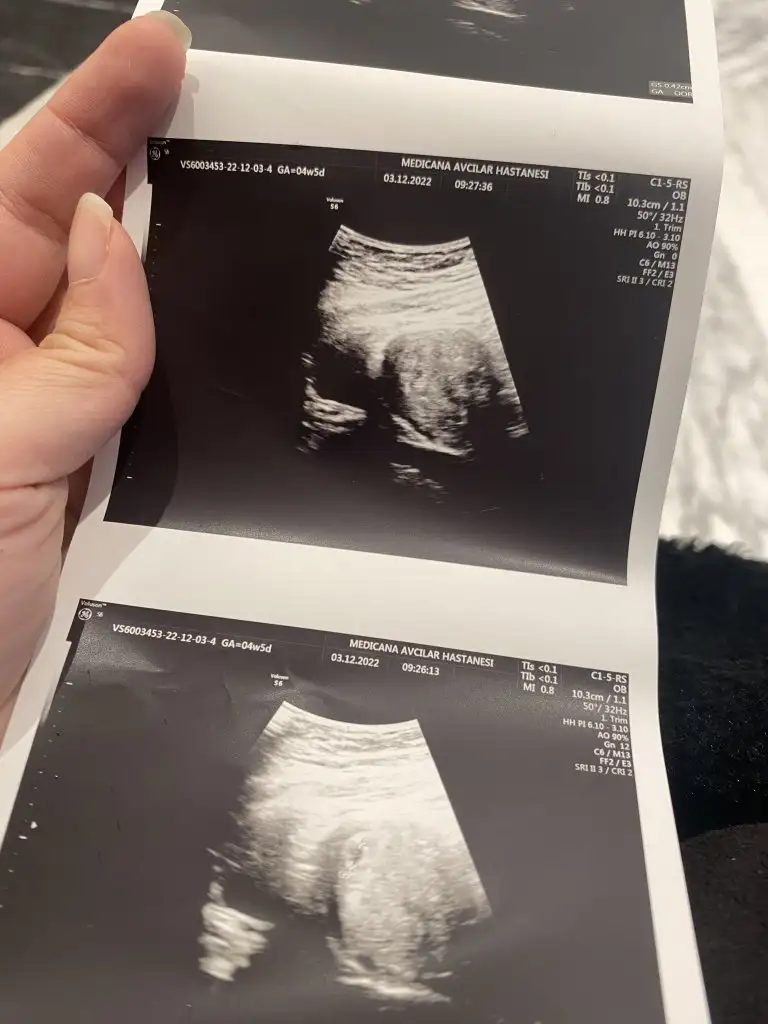

Günaydın gebelik testlerimde 2 çizgi çıktı dün sabah yaptığım koyuydu akşam farklı bir markada idrarımı bekletmeden yaptım silik de olsa 2.çizgi çıktı, bu sabah doktoruma gideceğim kan testi için, umarım orada da çıkar ve aranıza katılırım, bugün 4+1 olacak bu günlerde öğrenen varsa betası kaçtı acaba ☺️

Günaydın bende ağustos annesiyim eğer bir aksilik olmazsa geçen sene bu zamanlar kimyasal gecirdim 3 kasim başlama 8 kasim son şimdi kan verdim 2 saate belli olur

• 20221203_080243.webp

20221203_080243.webp

31,3 KB · Görüntüleme: 56